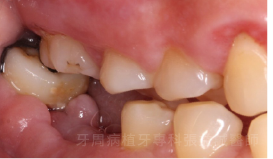

治療前 治療後

治療前

治療後